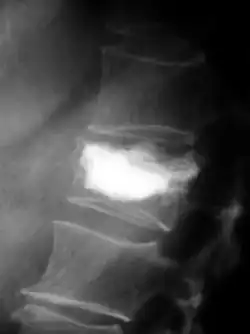

Pour le diagnostic initial, la radio X classique a une importance centrale. L'indication pour des projections sur deux plans est toujours donnée en cas de soupçon de tumeur osseuse[87]. Les métastases ostéolytiques sont caractérisées par une perte de densité osseuse. Ceci se reconnaît sur la radio par un noircissement plus élevé, en raison de la plus grande transparence aux rayons X. Inversement, les métastases ostéocondensantes présentent à cause de la plus grande densité osseuse un noircissement inférieur. Les métastases ostéolytiques sur la colonne vertébrale sont nettement plus difficiles à reconnaître : seulement quand environ 50 % de la densité totale de l'os a disparu[87].

Scanner d'une métastase ostéocondensante dans l'os du crâne d'un patient souffrant d'un carcinome de la prostate. On reconnaît clairement l'extension de la métastase au-delà des limites initiales de l’os.

Par comparaison, scanner de métastases ostéolytiques dans l'os du crâne d'une patiente souffrant d'un cancer du sein. On distingue une ostéolyse plus grande sur le front, et plusieurs plus petites.

Radio du bassin d'un patient atteint d'un carcinome de la prostate : multiples métastases ostéocondensantes, en particulier sur le sacrum, mais aussi sur l'ilion surtout gauche (à dr. sur l'image), sur la pointe de l'ischion gauche, et sur le fémur proximal gauche. On détecte à l'occasion une arthrose de hanche droite (à g. sur l'image).

Radio du bassin avec métastases ostéolytiques. Les métastases sont sur les deux fémurs et sur le bassin lui-même.